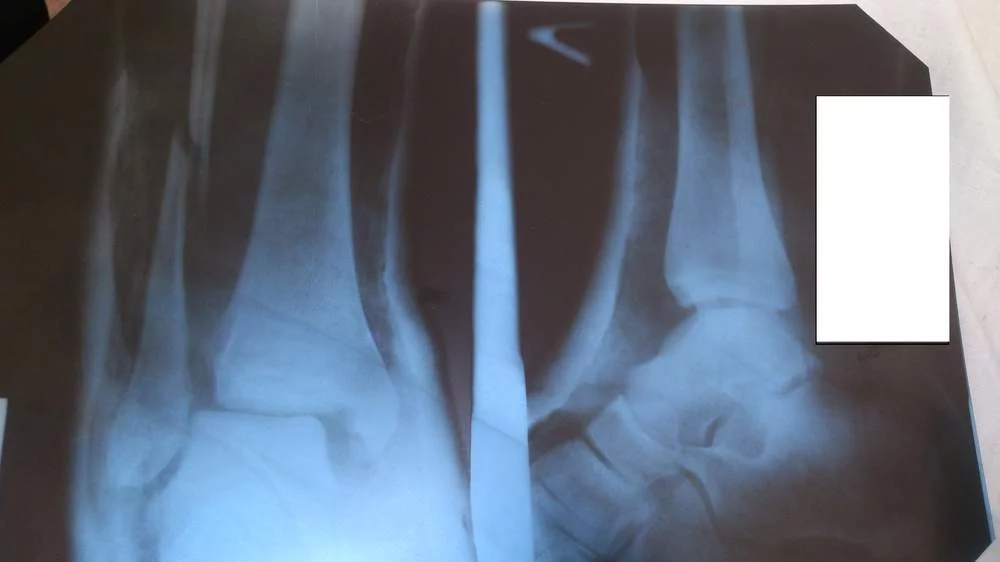

Диагноз:закрытый перелом наружной лодыжки левой голени с разрывом межберцового синдесмоза. 24.01. сделали операцию , поставили пластину . После 4х недель 21.02. сняли гипс и назначили лфк . 21.03. врач хочет меня выписать, и но я не могу еще обходится без костылей , и нормально передвигаться особенно в общественном транспорте. Работа у меня все время на ногах.